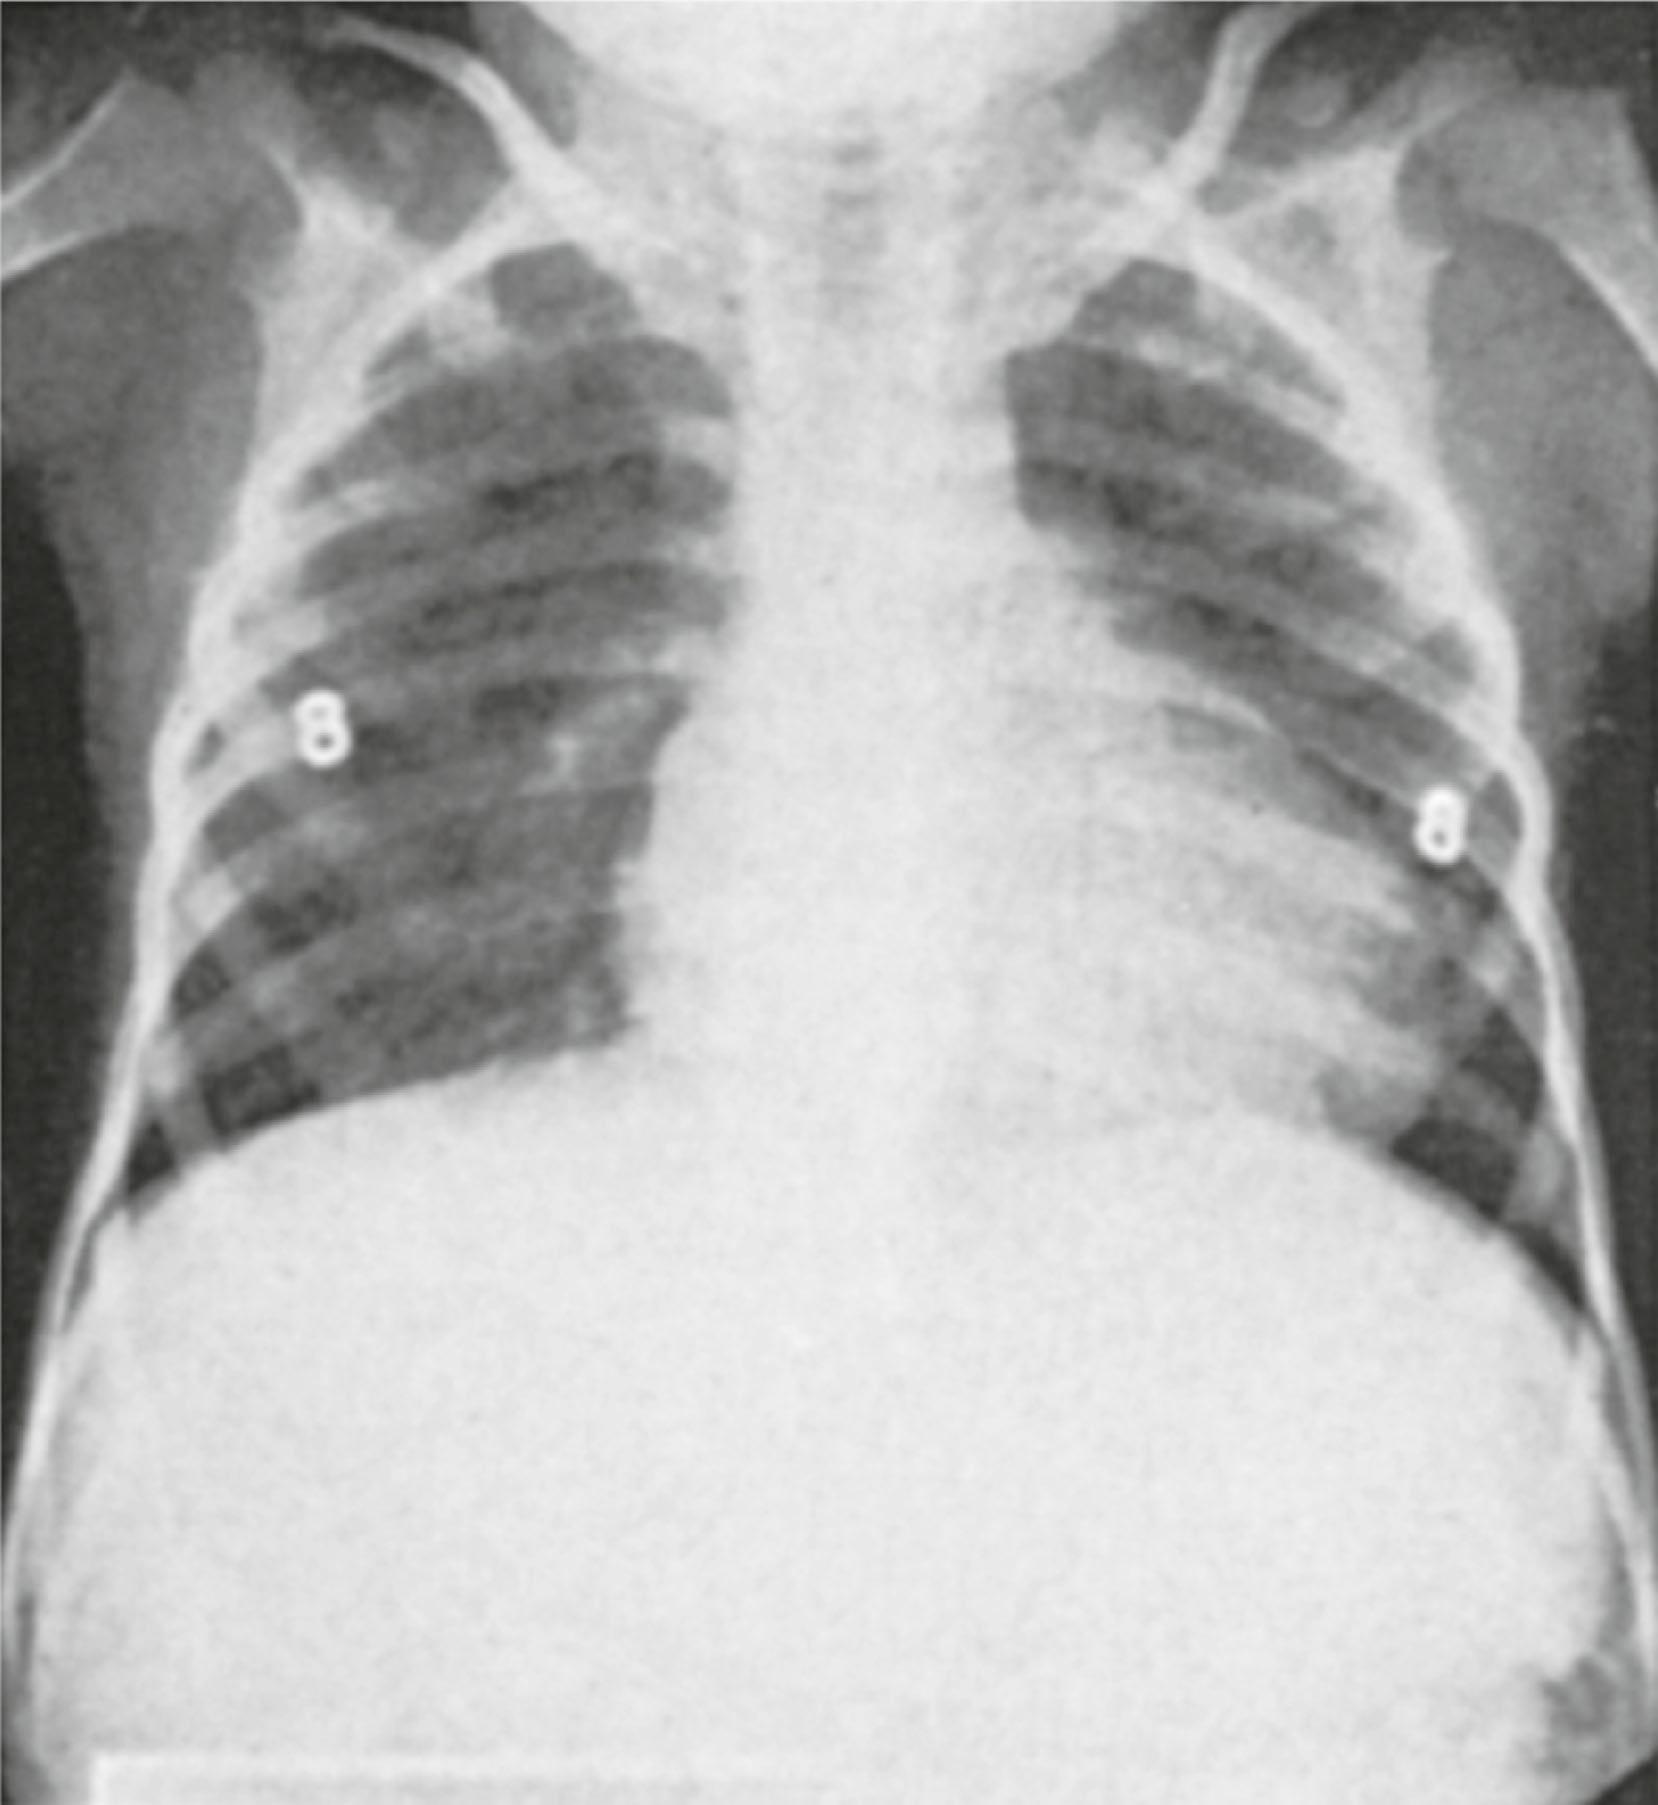

A familial occurrence of the polymastia anomaly has been observed. The association of polymastia with congenital cytogenetic syndromes, especially those involved with chromosomes 3 and 8, has been reported. Furthermore, other congenital anomalies, notably Turner syndrome (ovarian agenesis and dysgenesis with chromosomal karyotypes of 45,X, but mosaic patterns [45,X/46,XX or 45,X/46,XX/47,XXX] are seen) and Fleisher syndrome (lateral displacement of the nipples to the midclavicular lines with bilateral renal hypoplasia ) may include polymastia as a component ( Fig. 5.6 ).

Fig. 5.6, Fleisher syndrome. Posteroanterior chest roentgenogram of a 5-year-old with bilateral renal hypoplasia. Although the clavicles are not horizontal, the lateral displacement of the nipples (designated by the lead markers 8) is apparent.